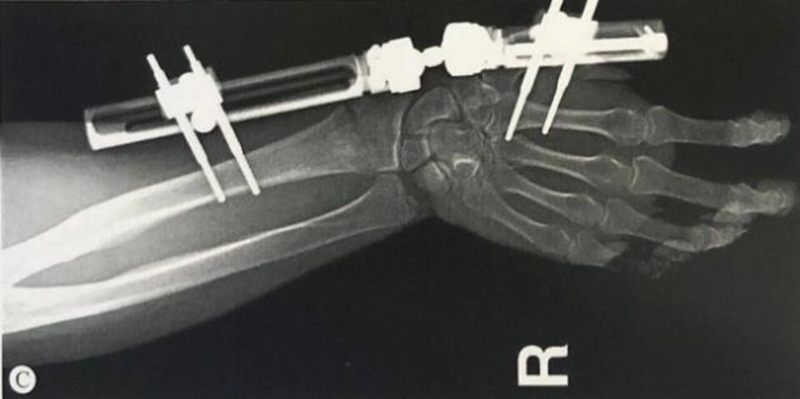

2、桡骨远端正常角度

掌倾10°至15°,尺偏20°至25°。

图1 尺偏角20°-25°,桡骨茎突比尺骨茎突高出约1.5cm